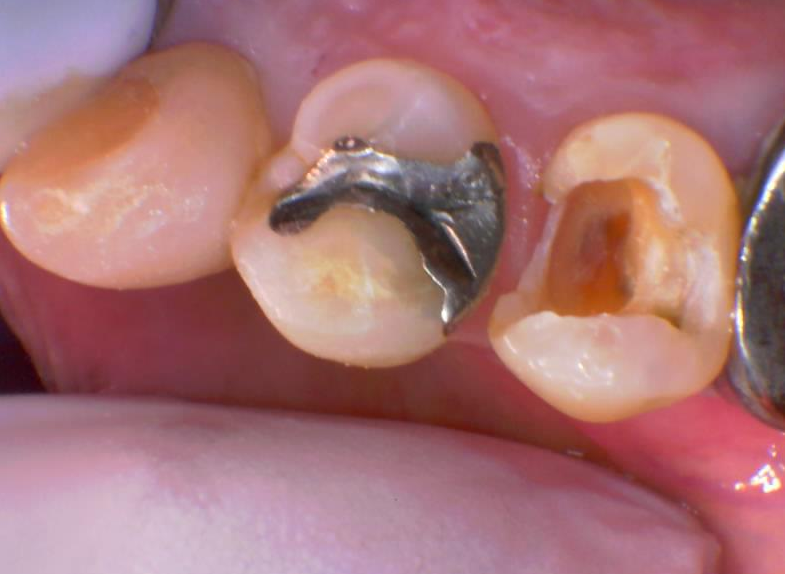

虫歯を削るとこのように大きな穴になりました。かなり大きく歯の神経近くまで削っています。正直今後痛みなどの症状が出た場合は歯の神経をとる処置(抜髄)が必要になる可能性が高いです。運よく銀歯が外れてくれてよかったです。銀歯の隙間に詰まった汚れから虫歯になり銀歯の下でゆっくり時間をかけて虫歯が進行していたため症状がでなかったのです。